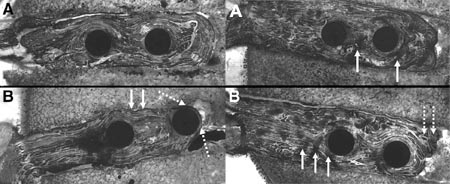

Recientemente Dargel y colaboradores realizaron un estudio biomecánico en donde se concluyó que la solidarización de los 4 haces del injerto a nivel proximal con sutura,disminuye el desplazamiento intratúnel descripto al utilizar dicho sistema de fijación, igualando al descripto para los sistemas de fijación colgante (Fig. 3).17 Cabe destacar que la fijación del injerto no solo debe cumplir los requerimientos biomecánicos, sino que también debe facilitar la incorporación biológica y en este sentido creemos que el sistema de fijación transfixiante cumple mejor estos requerimientos en comparación con el colgante, ya que con el primero logramos una fijación más anatómica (más cercana a la articulación) y el sistema nos posibilita realizar un mejor “press-fit” entre el injerto y el túnel facilitando de esta forma una más rápida incorporación.

Figura 3: Desplazamiento intratunel descripto por Dargel y col. Izq.: preparación sin suturas, der.: preparación con suturas. 3a: Antes y 3b: Después de los test biomecánicos.